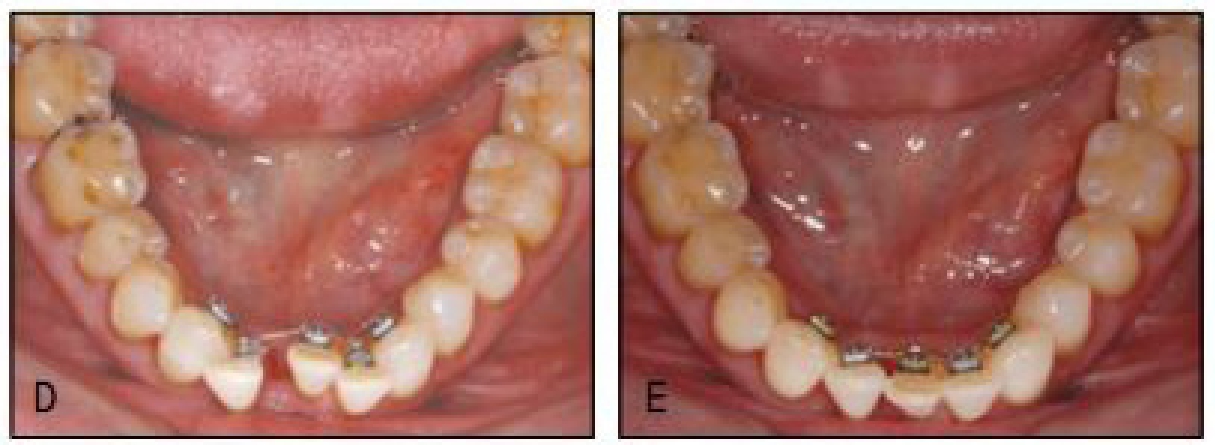

한편, 치주질환 등 병적 이유가 아니더라도 연령의 증가와 함께 치열은 변화를 보이고 있다. 정도의 차이가 있을 뿐이지 모든 환자들이 노화에 따른 치열 변화를 보이고 있다.

이러한 생리학적 변화는 하악 치열에서 두드러지게 나타나는데 악궁의 축소와 함께 하전치부 크라우딩의 증가가 초래된다. 이러한 크라우딩 증가는 치간골을 얇게 만들고 효율적인 치태 관리를 방해하여 치주질환으로 인한 골파괴를 촉진하는 바, 이를 해소하는 또는 이러한 일이 나타나지 않도록 소위 치주환경을 개선해 주는 교정치료가 고령자의 구강건강을 위해 반드시 필요하다.